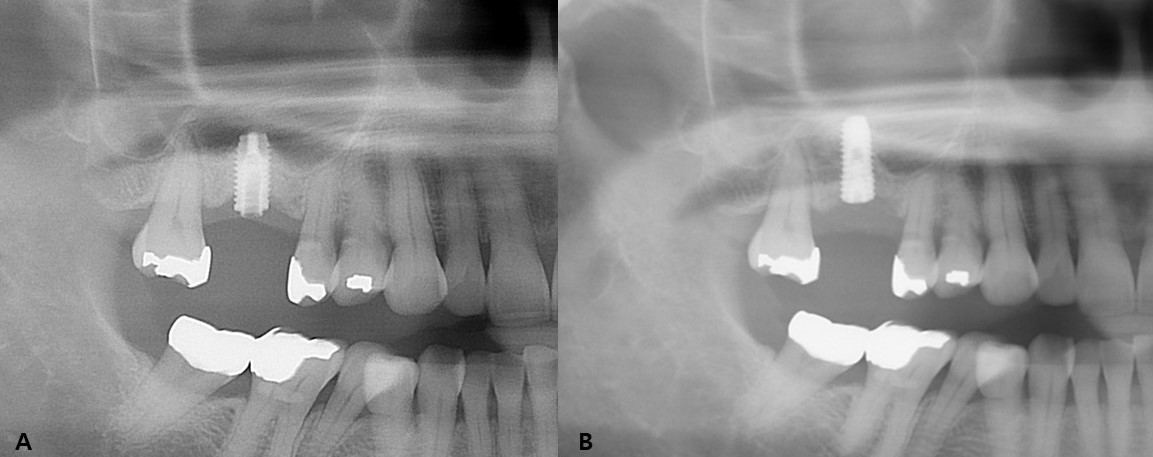

This study included 22 men and 11 women (mean age, 60.8 years; range, 33–82 years) with a total of 43 fractured implants (Table 1 and Fig. 1). The incidence of implant fracture was two times higher in men than in women (M:F = 22:11). Among the 33 patients, seven had external-connection implants, of which 12 were fractured (Fig. 2). Internal-connection implants were used in 26 patients, of which 31 were fractured (Fig. 3). Of the 26 patients with internal-connection implants, bone- and tissue-level fractures were observed in 23 and 3 cases, respectively. Maxillary and mandibular implant fracture occurred in 15 and 18 patients, respectively. Single- and multiple-implant fractures were observed in 26 and 7 patients, respectively. Except for two cases of anterior-implant fracture (Cases 9 and 12), all fractured implants were located in the premolar and molar regions (Table 1). In case 10, the fractured posterior single implant was removed through a typical implant removal process and socket preservation was performed using Bonplug® (Inobone Co.) (Fig. 4). Case 12 involved an anterior single-implant fracture with a clear fracture line (Fig. 5). In case 20, multiple fractured posterior implants were removed using an elevator (Fig. 6). In case 22, two fractured posterior implants were removed, and bone grafting was performed (Fig. 7).